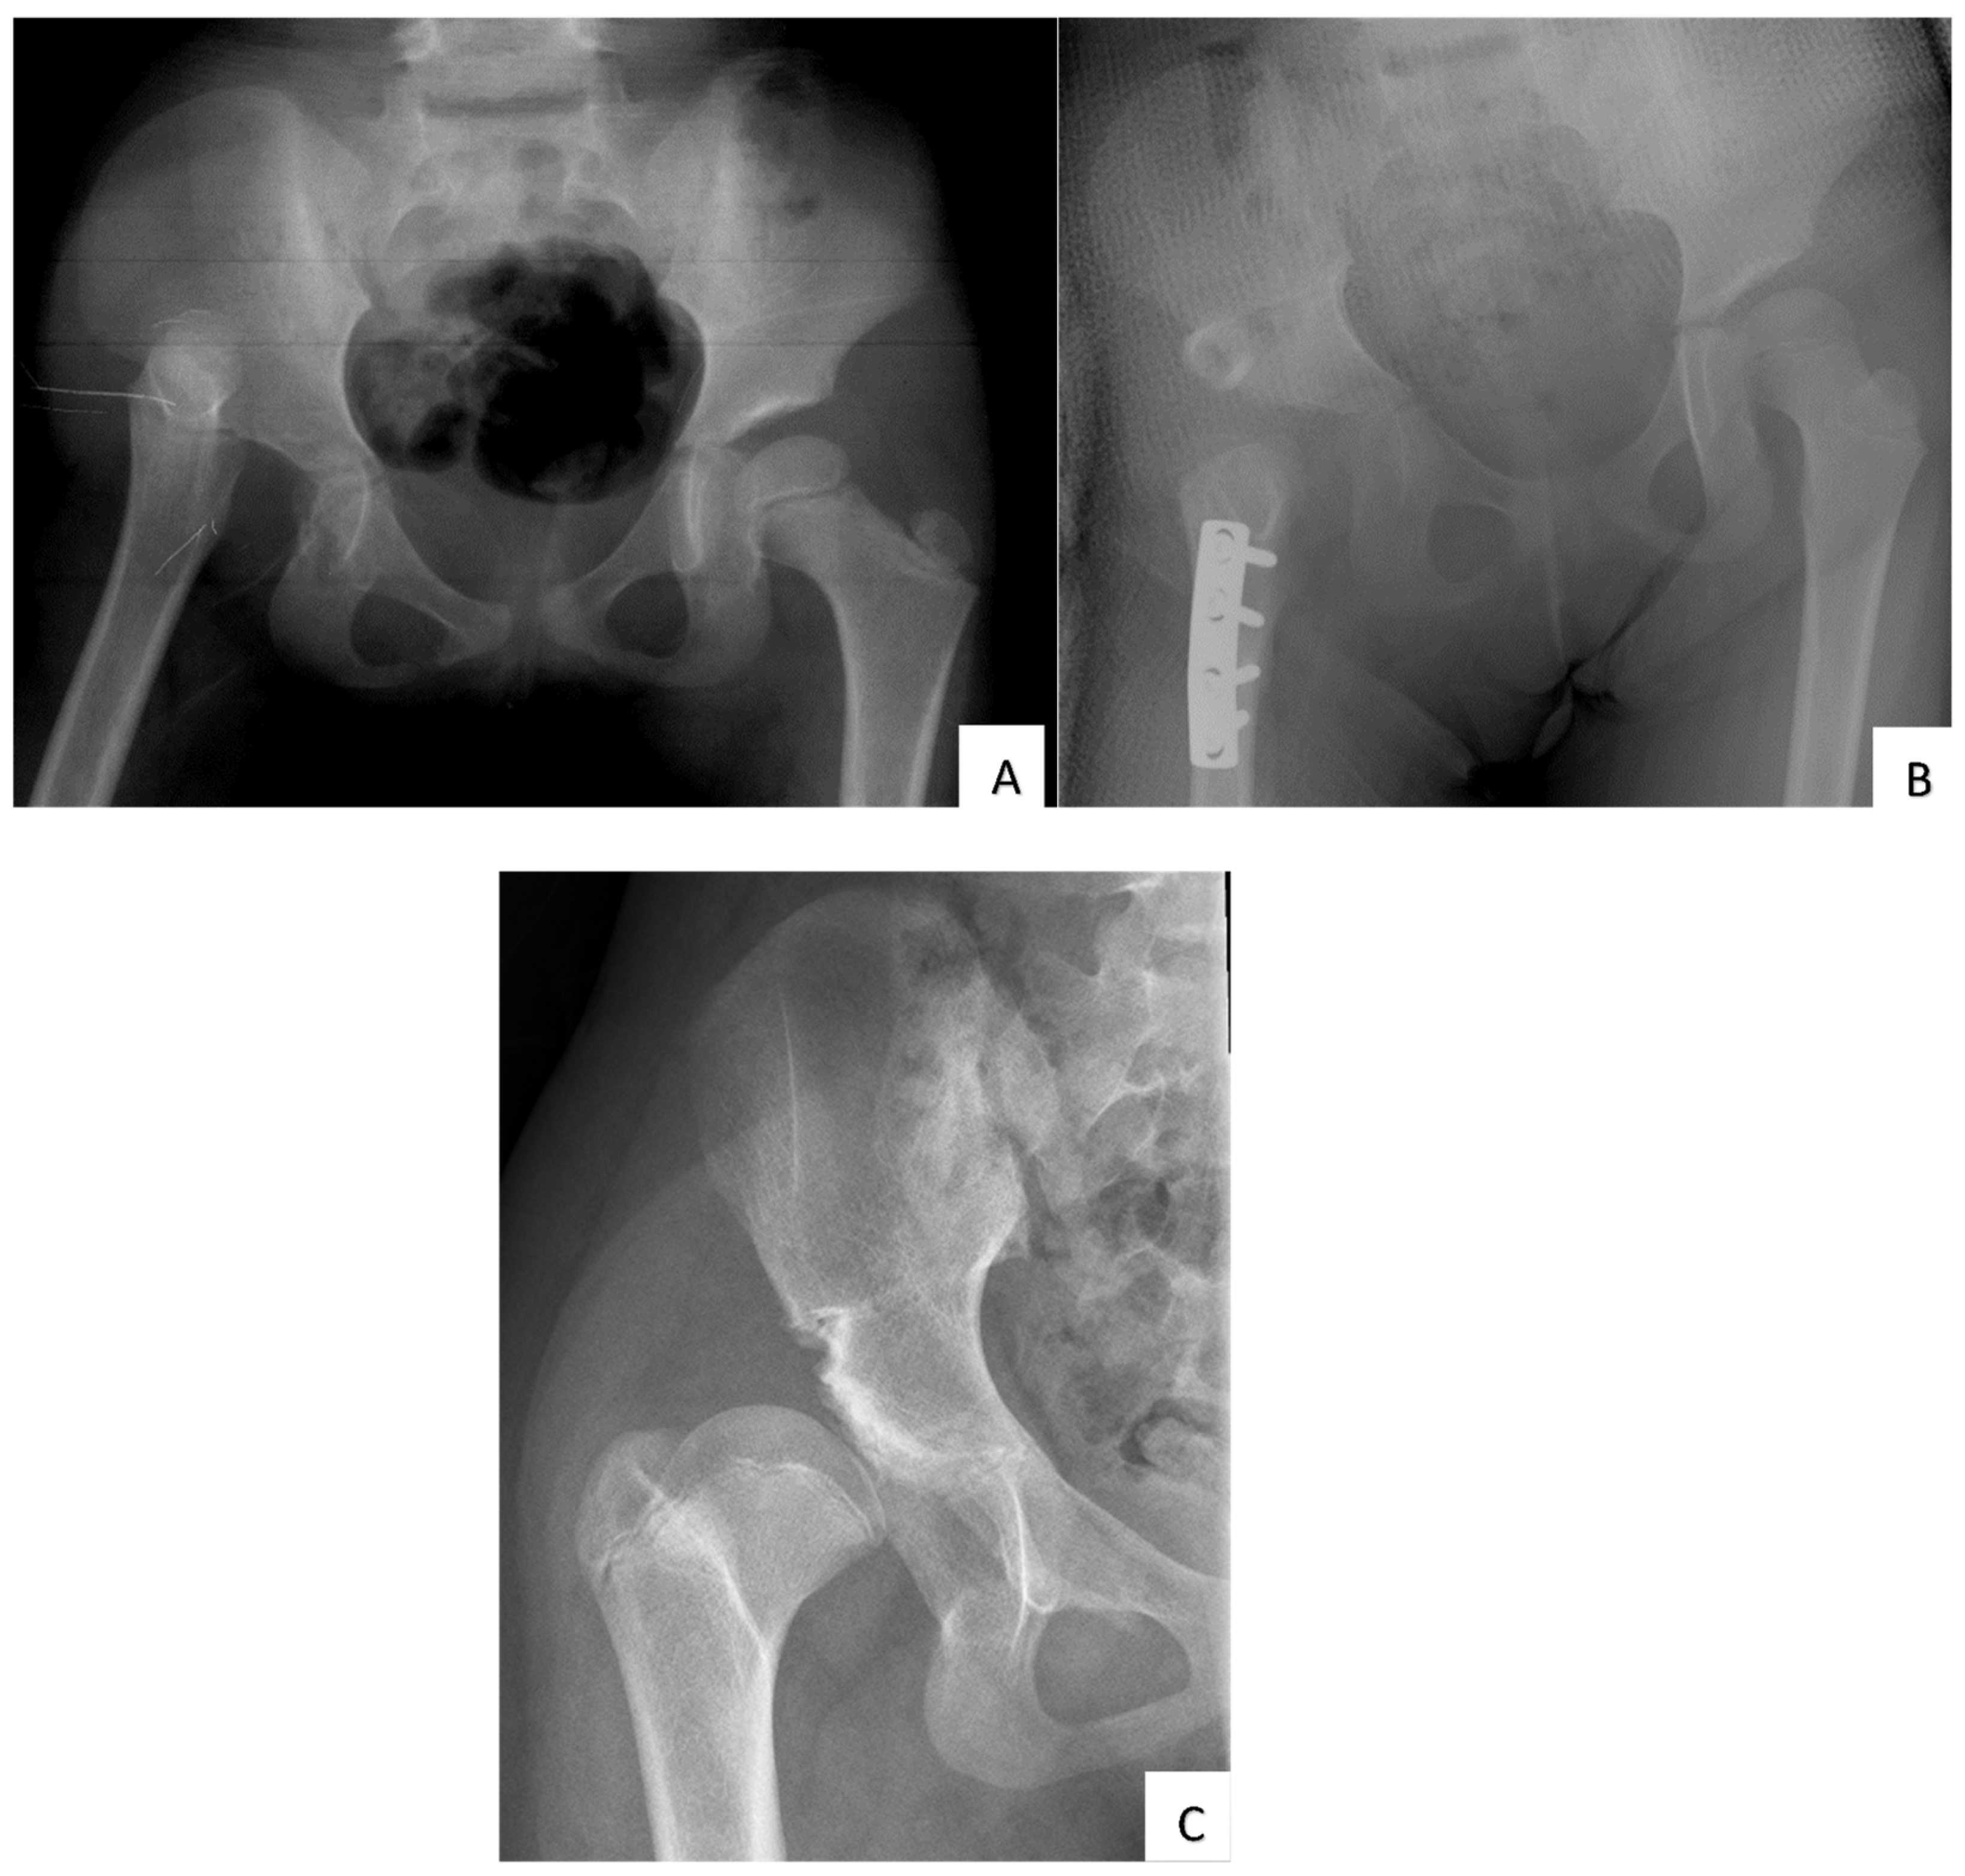

Outcome of Open Reduction Alone or with Concomitant Bony Procedures for Developmental Dysplasia of the Hip (DDH)

2. Materials and Methods

3. Results